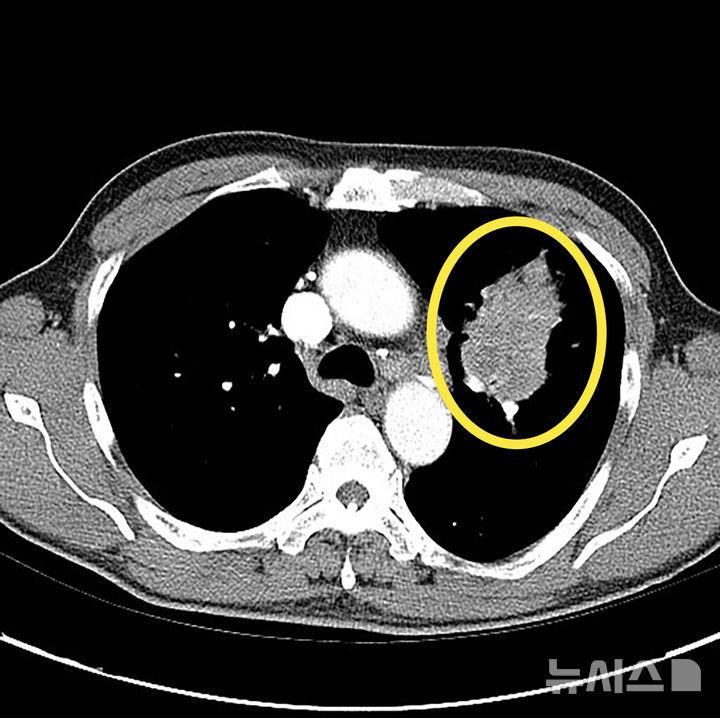

15일 의료계에 따르면 폐암은 폐에 비정상적인 암세포가 무절제하게 증식해 종괴(덩어리)를 형성하고 인체에 해를 미치는 것을 말한다. 폐암은 폐에 국한돼 발견되기도 하지만 진행될 경우 반대쪽 폐뿐 아니라 임파선이나 혈액을 통하여 뼈, 간, 부신, 신장, 뇌, 척수 등 온몸으로 전이될 수 있다.

하지만, 최근에는 비흡연자에게서도 폐암 발병이 증가하고 있어 증상이 없고 고위험군이 아니더라도 관심을 기울일 필요가 있다. 간접흡연이나 요리시 발생하는 연기, 라돈·석면 등 발암물질에 노출되는 직업 종사자나 미세먼지 노출시에도 폐암에 걸릴 수 있다. 저선량 흉부 CT(컴퓨터단층촬영)는 폐암 조기 진단에 매우 효과적인 수단으로 만성 폐쇄성 폐질환(CODP)이나 다른 암 병력이 있는 등 고위험군에서는 정기적인 검사가 권장된다. 저선량 CT는 환자에게 노출되는 방사선량을 6분의 1 수준으로 최소화한 장비다.

따라서 고위험군에서는 저선량 CT를 이용한 정기 검진이 매우 중요하다. 결절이 발견된다고 다 암으로 진행되는 것은 아니다. 결절은 암일 수도 있지만 염증, 섬유화, 림프절 비대, 과거 결핵 흔적 등 다양한 원인으로 생길 수 있다. 특히 폐암 고위험군이라면 호흡기알레르기내과 전문의에게 진료를 받아 정확한 평가를 받는 것이 필요하다.